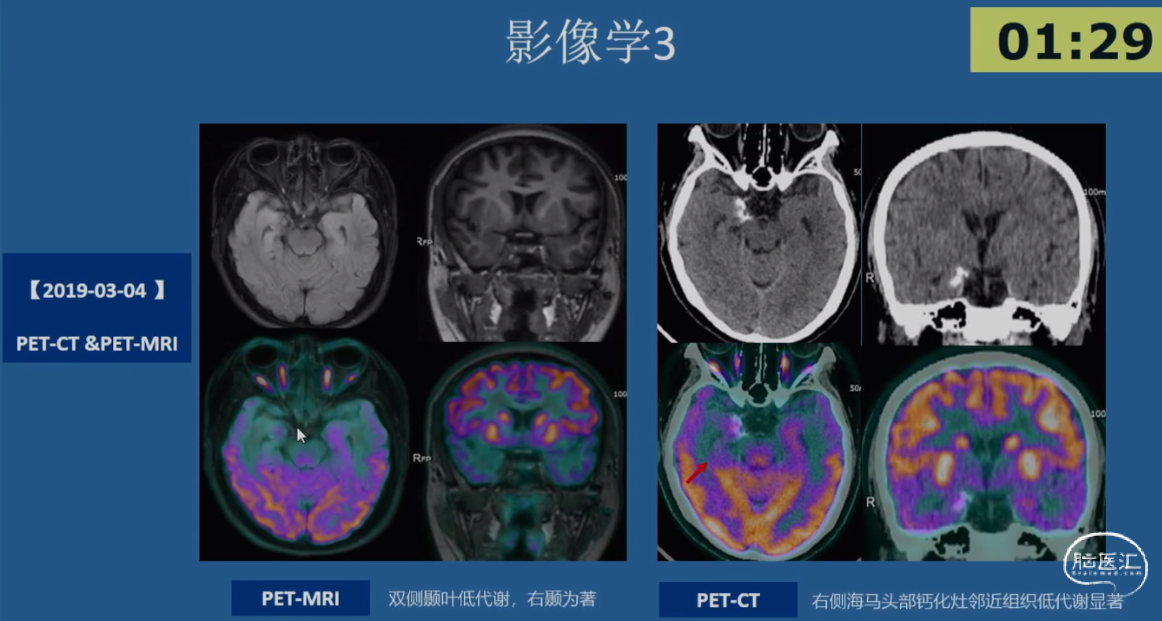

病例示例3 -简要病史

•患者,女性,20岁,右利手

•起病年龄:出生4月

•主要发作形式:伴有知觉受累的局灶性发作

-发作主要表现:发作前偶伴心悸、胸闷→后出现意识丧失伴眼神呆滞→数秒后出现身体向各方向不自主扭转,伴喉部发声(无四肢抽搐表现)→发作持续5-10min后意识恢复→发作后无头痛、头晕等不适

-【出生4月起】:初始发作频率1次/天,服用CBZ后发作可控;

-【12岁起】:发作频率再次↑为1次/天,加用药物后发作控制于5-10次/年;

-【19岁起】:多药联用控制不佳,发作频繁时可达3-4次/天,至少2-3次/月

•20岁时AEDs服用:CBZ 0.2g tid + LTG 100mg bid +CZP 0.5mg qn po

•既往史及家族史无殊,无热性惊厥史

•出生史:剖腹产,无早产、难产史,生长发育同同龄人;学历中专

•认知功能测评:MMSE 27分(延迟记忆-3),MoCA 27分(抽象-1,延迟回忆-2);WAIS-RC IQ 100分(语言IQ 92分;操作IQ 112分)

•情绪测评:HAMA 9分(轻度焦虑),HAMD 8分(轻度抑郁)

01.初步评估:

影像学表现:2018-03-05 MRI 常规MRI阴性

02.发作期评估

03.SEEG手术评估